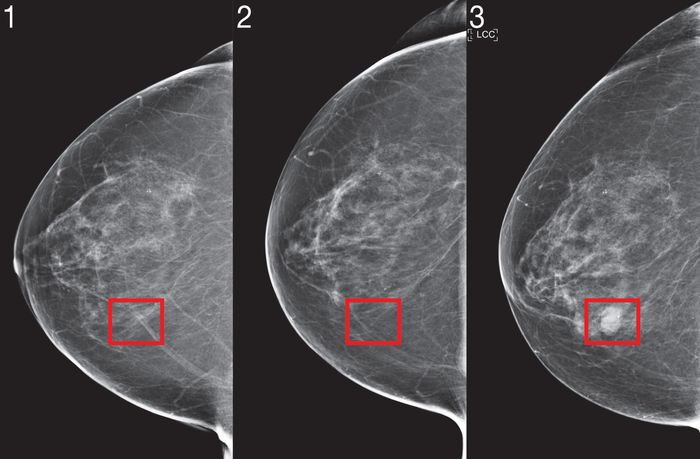

Thuật toán phân tích các hình ảnh siêu âm trước đó, và dường như hoạt động ngay cả khi bác sĩ không nhận thấy dấu hiệu cảnh báo trong những lần quét trước đó. “Những công cụ Trí Tuệ Nhân Tạo đang làm là họ đang trích xuất thông tin mà mắt và não tôi không thể,” cô nói.

Thuật toán MIT phân tích bốn góc nhìn tiêu chuẩn trong một hình ảnh siêu âm, từ đó suy luận thông tin về bệnh nhân thường không được thu thập, chẳng hạn như lịch sử phẫu thuật hoặc yếu tố hormone như mãn kinh. Điều này có thể hữu ích nếu dữ liệu đó chưa được thu thập bởi bác sĩ trước đó. Chi tiết về công việc được trình bày trong một bài báo được xuất bản ngày hôm nay trong tạp chí Y học Chuyển giao Khoa học.